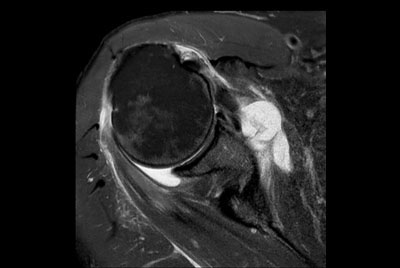

Shoulder with oncologic mass